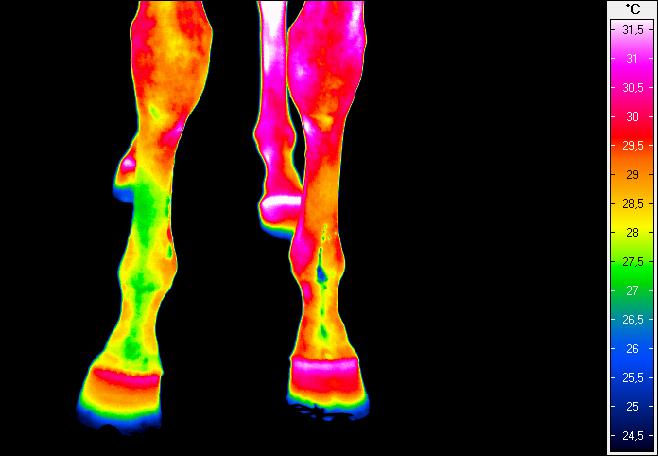

Termografia umożliwia nieinwazyjny pomiar rozkładu temperatury na powierzchni ciała konia. Wynikiem badania jest obraz – termogram, w którym poszczególne barwy odpowiadają określonym zakresom temperatur. Uzyskany rozkład cieplny odzwierciedla przede wszystkim ukrwienie tkanek powierzchownych, aktywność metaboliczną mięśni oraz właściwości izolacyjne skóry i okrywy włosowej.

W warunkach prawidłowych rozkład temperatury ciała konia charakteryzuje się wysokim stopniem symetrii pomiędzy lewą i prawą stroną. Najwyższe wartości temperatur obserwuje się w okolicach dobrze unaczynionych, takich jak oczy, nozdrza czy większe masy mięśniowe, natomiast najchłodniejsze obszary obejmują dalsze odcinki kończyn. Odstępstwa od tego wzorca – zwłaszcza asymetrie przekraczające około 1°C – mogą wskazywać na zaburzenia fizjologiczne lub rozwijające się procesy zapalne.

W medycynie weterynaryjnej i fizjoterapii najszersze zastosowanie termografia znalazła w ocenie dalszych odcinków kończyn, które są szczególnie narażone na urazy w trakcie treningu i użytkowania sportowego.

Metoda ta pozwala na identyfikację obszarów o podwyższonej temperaturze, związanych z zapaleniem ścięgien, więzadeł, torebek stawowych czy okostnej, często jeszcze przed pojawieniem się wyraźnych objawów klinicznych. Oprócz kończyn, istotnym obszarem zastosowania termografii jest grzbiet konia. Zaburzenia w obrębie mięśni przykręgosłupowych, więzadeł nad- i międzykolcowych czy stawu biodrowo-krzyżowego często mają charakter złożony i nie zawsze są łatwe do jednoznacznego rozpoznania przy użyciu standardowych metod. Termografia umożliwia wizualizację zmian w aktywności cieplnej tych struktur, co może wskazywać miejsca przeciążenia, bólu lub kompensacji ruchowych.

W praktyce szczególnie cenne okazuje się wykorzystanie termografii w przypadkach, gdy problemy kończyn i grzbietu wzajemnie na siebie oddziałują. Analiza całościowego rozkładu temperatury ciała pozwala spojrzeć na konia jako na funkcjonalną całość, a nie jedynie zbiór odrębnych struktur anatomicznych.